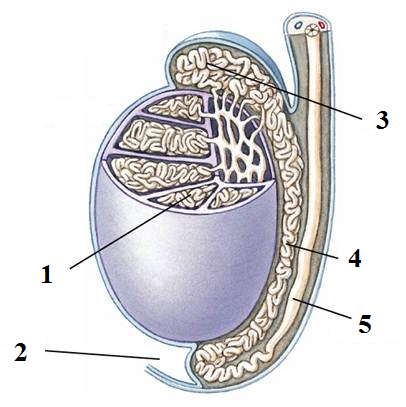

Afferent/efferent arteriole

Calyx (of the kidney)

Collecting duct

Descending/Ascending loop (of nephron)

Distal (convoluted) tubule

Epididymis

Glomerular capsule (=Bowman's capsule)

Glomerulus (=glomerular capillaries)

Juxtaglomerular apparatus

Nephron

Peritubular capillaries

Proximal (convoluted) tubule

Renal artery/vein

Renal capsule

Renal columns

Renal corpuscle

Renal cortex

Renal medulla

Renal Pelvis

Seminiferous tubule

Testis (s.) Testes (pl.)